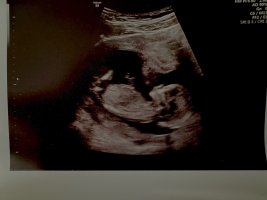

Ser kun beina :/Er det mulig å se kjønn her? 13+3

Ser ut som guttSyns det er veldig vanskelig å se, altså. Noen som vil gjette? Første ul uke 11, andre uke 14.